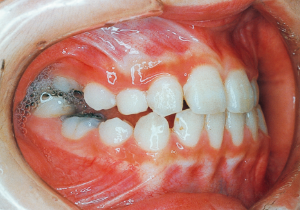

9 7-28-’82 After Phase 1 Treatment 11 years old

Aware that treatment would be challenging, we proceeded with the first phase of treatment based on the current functional status and anticipated developmental implications (7). During the mixed dentition phase, the body responds readily to treatment, allowing for relatively rapid tooth movement and changes in jaw position (8,9). Subsequently, once freed from mechanical stimulation, growth continues according to inherent predispositions, often appearing to disregard occlusal functional efficiency (10,11). These changes are clearly observable on cephalometric radiographs (12). After confirming the extent and direction of growth, we decided to incorporate surgical intervention into the treatment plan and wait until the age when growth begin to decline.